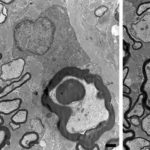

Immagine, sei giorni dopo il trattamento con IGF-1 trasportato da nanoparticelle di dendrimero (blu), le particelle sono penetrate attraverso la cartilagine dell’articolazione del ginocchio. Credito: Brett Geiger e Jeff Wyckoff.

Quando queste particelle vengono iniettate in un’articolazione, ricoprono la superficie della cartilagine e iniziano a diffondersi attraverso di essa. Grazie alle catene PEG flessibili sulla superficie che coprono e scoprono la carica mentre si muovono, le molecole possono staccarsi brevemente dalla cartilagine, consentendo loro di spostarsi più a fondo nel tessuto.

La cartilagine nelle articolazioni dei ratti ha uno spessore di circa 100 micron, ma i ricercatori hanno anche dimostrato che le loro particelle potrebbero penetrare frammenti di cartilagine fino a 1 millimetro, lo spessore della cartilagine in un’articolazione umana.